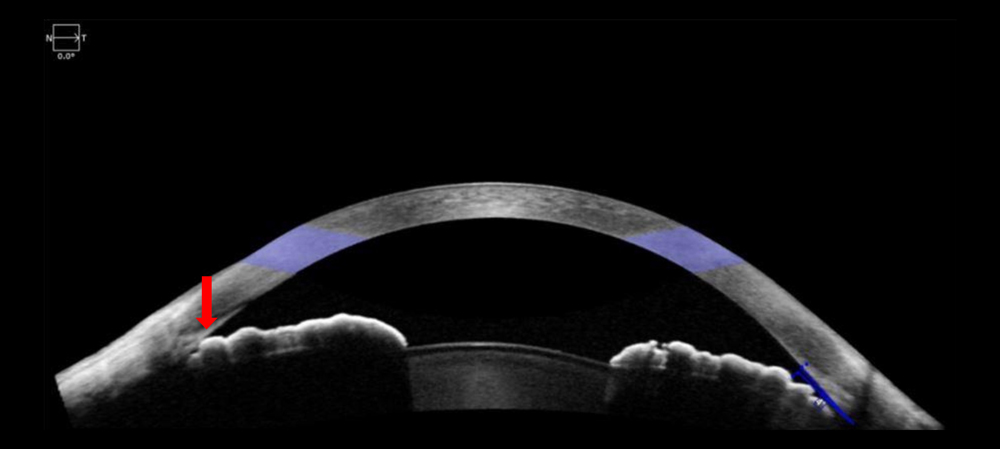

He offered this example: โIf an asymptomatic patient has anatomically narrow or closed angles determined during an eye exam, the imaging obtained would enable the physician to educate and counsel the patient of their condition, including intervention, as it would be difficult to explain to the patient otherwise. The image demonstrating angle closure would enable a provider to offer the patient options including 1) observation if asymptomatic; 2) laser iridotomy to open the drain as a preventative measure or if symptoms warrant the drain to be opened; 3) if appropriate, the need to perform cataract surgery to anatomically open the drain. This could also be a discussion in the setting of a patent iridotomy, yet the drain remains closed, and the patient is symptomatic with elevated eye pressure that needs to be lowered.โ

From a diagnostic standpoint, Dr. Shareef said imaging technologies can be helpful for patients who cannot have office-based gonioscopy, such as those who have a shallow or hypotonus eye. Imaging can help identify the location and size of cyclodialysis cleft for surgical planning, for example, or angle closure in the setting of a patent iridotomy in the presence of plateau iris syndrome. โ[Imaging] would enable the physician to counsel the patient to consider argon laser iridoplasty to further open the angle to enhance outflow and lower the eye pressure,โ Dr. Shareef said.